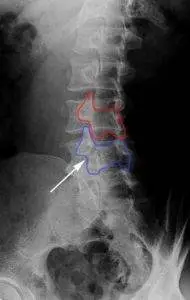

X-rays revealing “Scotty Dogs” with a visible fracture line in the pars area help diagnose spondylolysis. This sign highlights the pars area’s susceptibility due to its thinner structure. Below you can see in red the intact “Scotty Dog”. In purple, the neck of the “Scotty Dog” is broken as seen by the white arrow.